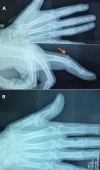

From the functional standpoint, the hand is one of the most important organs of the body. However, its significance depends largely upon the pincer action of the thumb-index. The management of traumatic lesions of the hand is nowadays' subject of numerous scientific discussions. We present here the case of a patient with a recent laceration of the central slip of the extensor tendon with boutonniere deformity linked to a dislocated interphalangeal thumb of the same hand with a loss of force of the clip thumb and index finger. This combination is a rare lesional of the traumatic hand that has not been previously reported in any orthopedic literature. It was observed after adopting the orthopedic treatment that the range of motion of its joint was at the same level as its healthy side without observing any redislocations during the 6-month follow-up period.